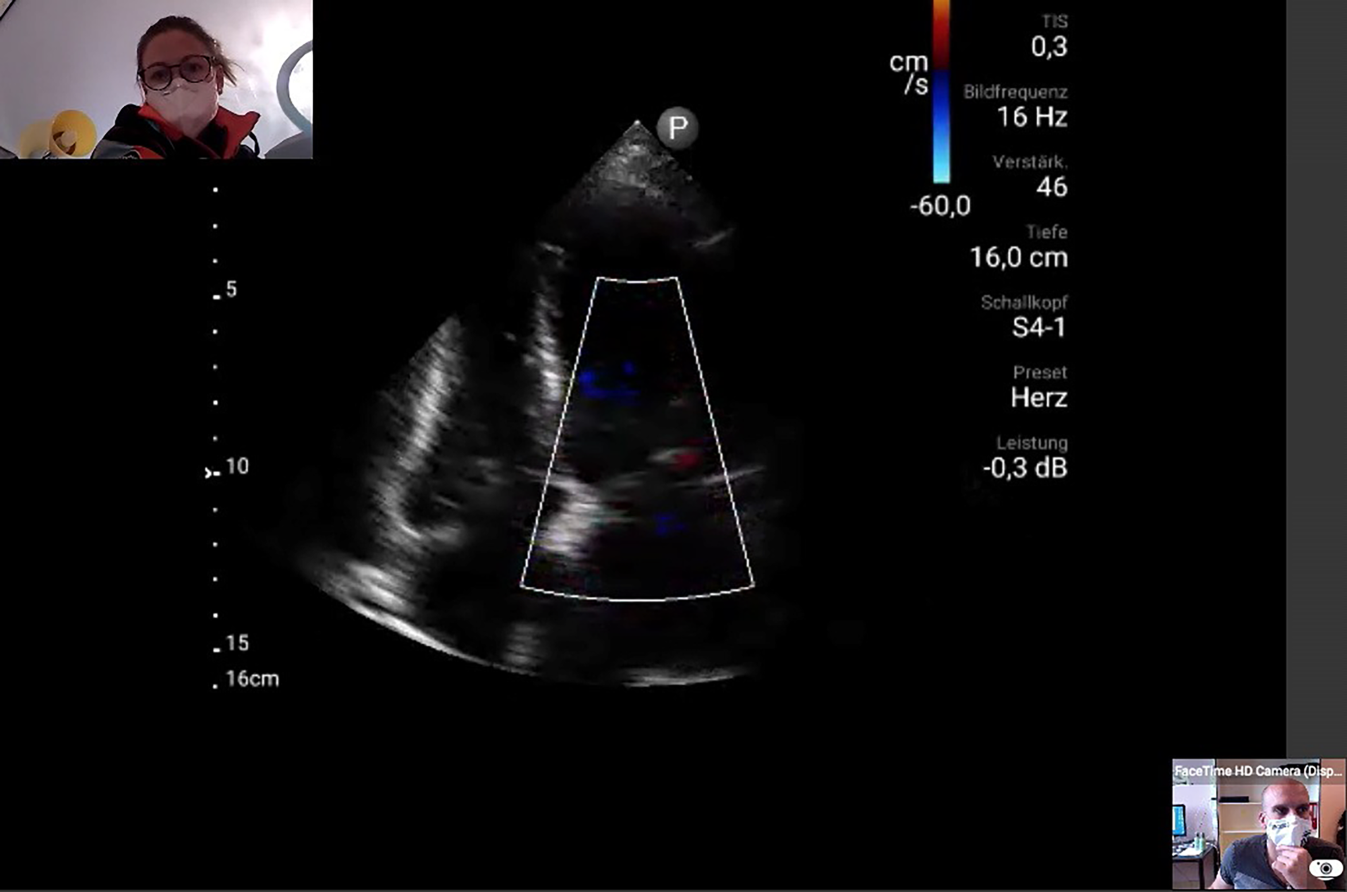

Abb. 1

Live-Übertragung einer Ultraschalluntersuchung: Zeitgleich zur Übertragung des Ultraschalls findet ein Videoanruf statt. Notärztin Dr. Martina Hermann (o. l.) und Ultraschallexperte PD Dr. Thomas Hamp (u. r.) können sich im Ärzt:innenteam austauschen